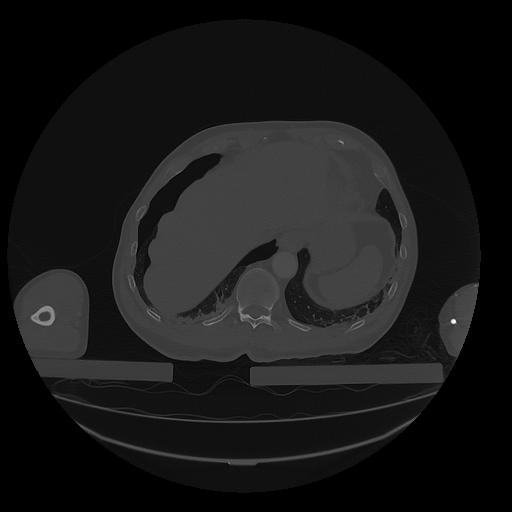

31 PULMON,CE,Vol,1.0,PULMON,,